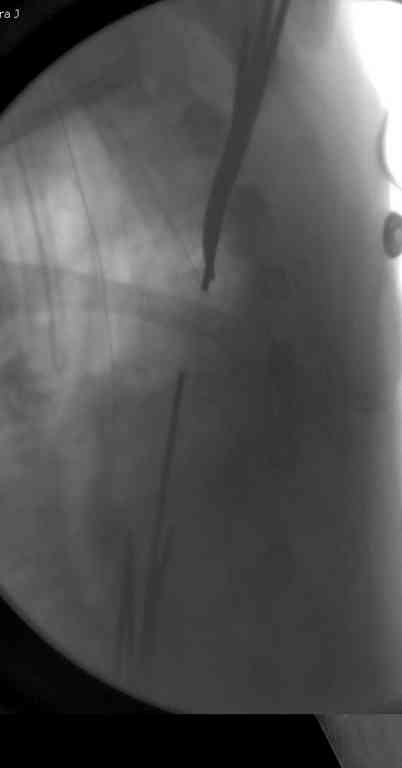

Неправильно выбранная тактика по фиксации или технические ошибки во время операции могут привести к серьезным осложнениям. Здесь привожу

пример из нашей практики, вроде обычный перелом шейки, фиксированный популярным методом "Сиэтла" - множественными спицами 2.8 мм с резьбой на конце.

При первичном осмотре в поликлинике через 3 недели обнаружили миграцию двух спиц, срочно госпитализированному на второй день перед операцией на всякий случай сделали снимок, одна спица находилась под ключицей в шейном отделе (на снимке).